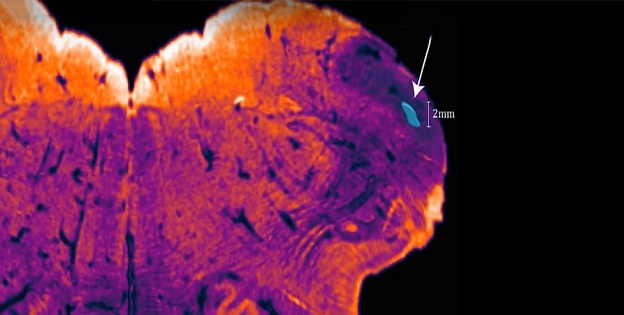

Neuroscientist George Paxinos and his team at Neuroscience Research Australia (NeuRA) have named their discovery the endorestiform nucleus – because it is located within (endo) the inferior cerebellar peduncle (also called the restiform body). It’s found at the base of the brain, near where the brain meets the spinal cord.

This area is involved in receiving sensory and motor information from our bodies to refine our posture, balance and movements.

“The endorestiform nucleus is all too evident by its dense staining for [the enzyme] acetylcholinesterase, all the more evident because the surrounding areas are negative,” Paxinos explained.